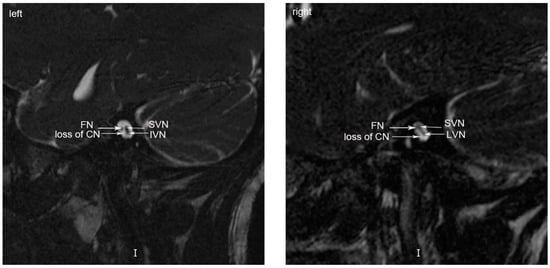

1.1. Case 1

1.2. Case 2